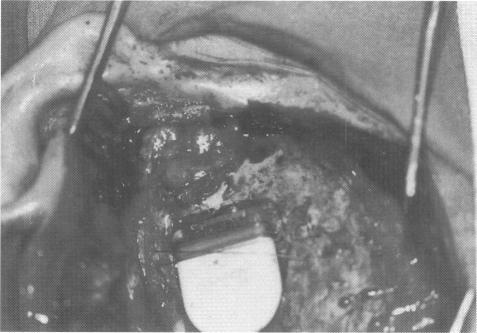

Normally, active chronic suppurative otitis media is regarded as a contraindication for cochlear implantation. In case of a radical cavity after surgical treatment for cholesteatoma, the electrode covered by the epithelial lining of the mastoid will likely become exposed or extruded. Under these circumstances we suggest the subtotal petrosectomy, obliteration of the middle ear cleft with abdominal fat, and the blindsac closure of the external ear canal before cochlear implantation.Fourteen patients with chronic otitis media were successfully implanted with an intracochlear multichannel cochlear implant. After an average follow-up of 28 months a temporary facial palsy in one patient and an insufficient closure of a retroauricular fistula over the mastoid cavity in two cases were observed as postoperative complications. One patient with a tumefactive inflammatory pseudotumor developed a massive inflammation in the implanted ear 2 months after surgery which could not be controlled by conservative treatment. The implant had to be removed and after administration of cyclophosphamide she could be successfully reimplanted 7 months later.Implantation of a foreign body in a potentially infected space which communicates with the endocranium means a surgical challenge which can be managed by obliteration of the middle ear. In case of massive inflammation we prefer a two-stage procedure.

通常情况下,活动性慢性化脓性中耳炎被视为人工耳蜗植入的禁忌证。在胆脂瘤手术治疗后形成根治性鼓室腔的情况下,被乳突上皮衬里覆盖的电极可能会暴露或脱出。在这种情况下,我们建议在人工耳蜗植入前进行颞骨次全切除术,用腹部脂肪封闭中耳腔,并对外耳道进行盲袋封闭。14例慢性中耳炎患者成功植入了鼓室内多通道人工耳蜗。平均随访28个月后,观察到1例患者出现暂时性面瘫,2例患者乳突腔上方耳后瘘管闭合不全,为术后并发症。1例患有肿胀性炎性假瘤的患者在术后2个月植入耳发生严重炎症,保守治疗无法控制。不得不取出植入物,在给予环磷酰胺后,7个月后她得以成功再次植入。在与颅内相通的潜在感染空间植入异物意味着一项手术挑战,可通过封闭中耳来解决。在发生严重炎症的情况下,我们更倾向于采用两阶段手术。